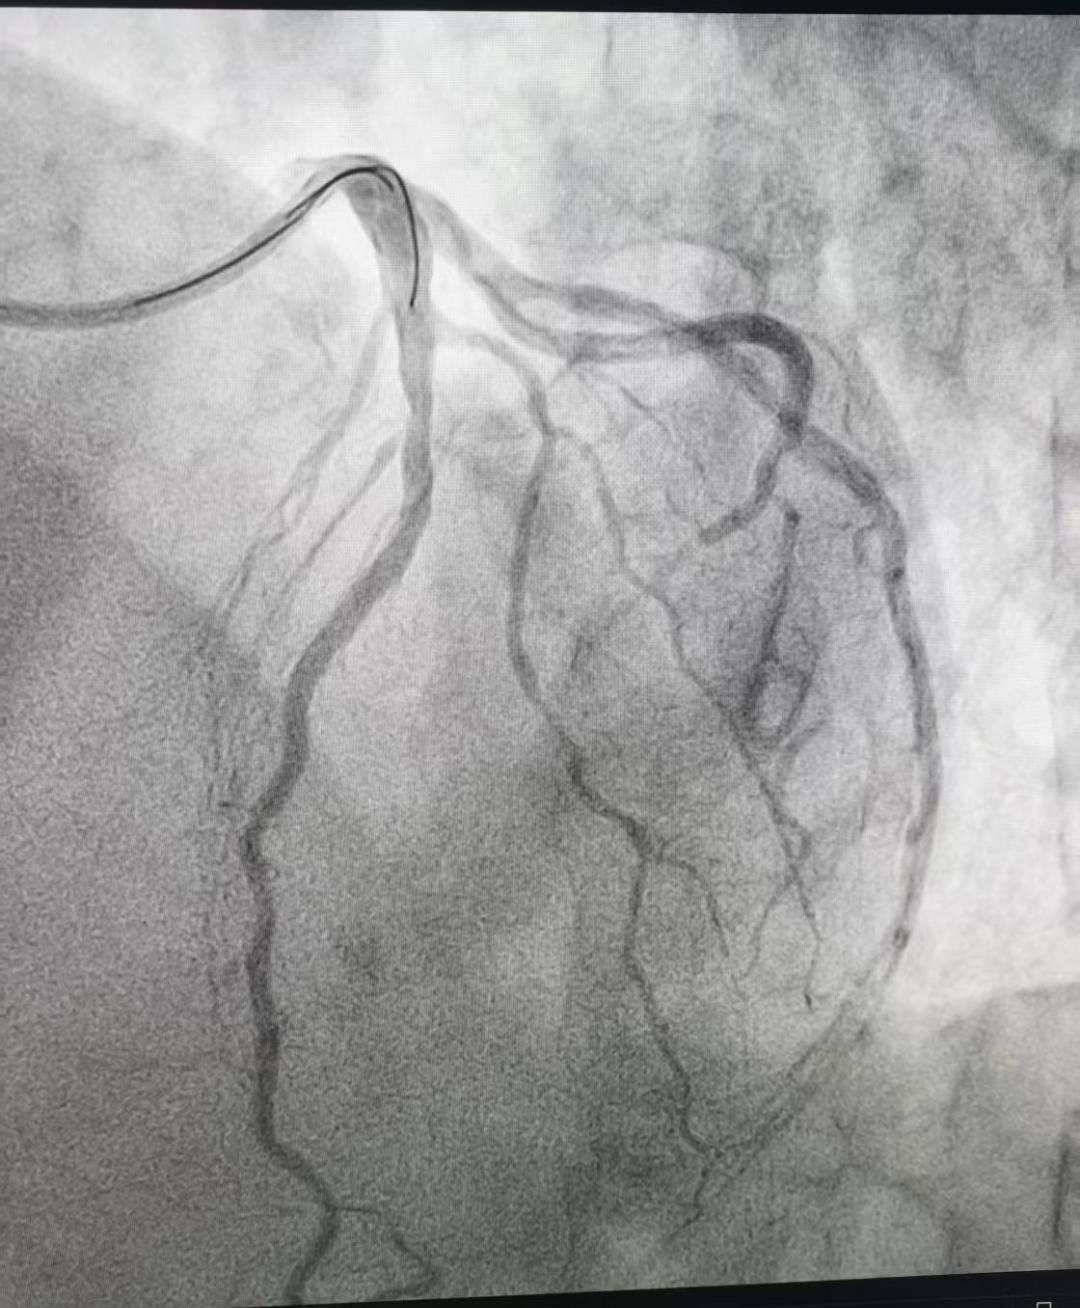

“时间就是心肌,时间就是生命!”心内三科谈金强主任和张用之主治医师立即启动急救绿色通道,为患者急诊行冠状动脉造影(CAG)以明确冠脉病情。造影结果显示:患者对角支自开口处100%闭塞!如此隐蔽的病变,不仅极度考验术者的观察力,更对冠脉解剖结构的熟悉程度提出极致挑战,稍有疏忽便可能漏诊,酿成不可挽回的结果!

张用之主治医师第一时间与患者家属细致沟通病情,在征得同意后,立即为患者施行经皮冠状动脉药物球囊扩张成形术。手术全程顺利,患者术后未出现任何不适症状。9月4日查房时,刘大娘的牙痛症状已完全消失,身体状态稳步恢复。